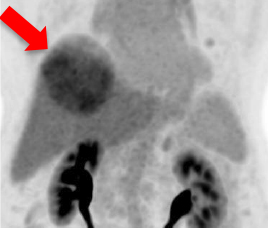

- 治療前Tc MAA SPECT/ CT

- 預測腫瘤與非腫瘤釔90粒子分佈

- 識別分流至肺部及內臟

- 使用鍀99m MAA(左)模擬釔90粒子分佈(右)

- 評估治療可行性

- 由雙示踪劑正電子/電腦雙融掃描計算處方劑量